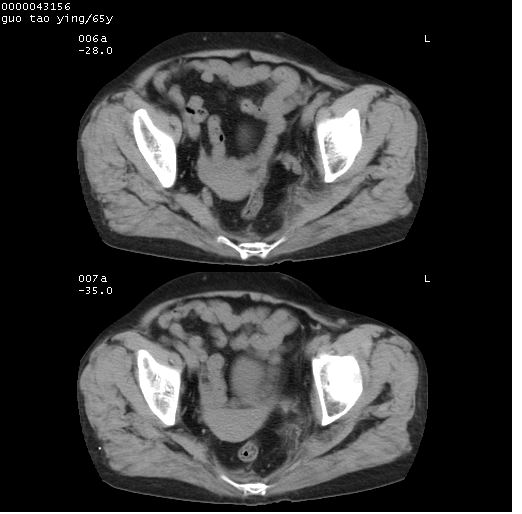

以下是引用黑白光影在2008-1-30 13:22:00的发言:[br]支持左耻骨骨折。[br]未见骶骨骨质明确破坏改变。[br]经楼主提示(勿局限于外伤)。考虑为右侧腹股沟直疝。[br][br][br][br]